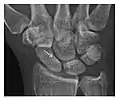

High-energy trauma fractures

Figure 3: A 26-year-old man presenting with wrist pain after being assaulted. (a) Initial anteroposterior radiograph shows a subtle linear lucency within the scaphoid extending to the scaphocapitate articular surface that was overlooked (arrow). (b) Initial "scaphoid" view was negative. (c) Followup anteroposterior radiographs, 12 days later, shows obvious scaphoid fracture (arrows).[1]

Triquetral fracture usually occurs on the dorsal aspect by impingement from the ulnar styloid or avulsion of strong ligamentous attachment. The dorsal avulsion fracture or "chip fracture" appears as a small bony fragment on the dorsal aspect of the triquetrum and is best detected on the lateral view(Figure 4). When radiography is negative in patients with high suspicion of a fracture, both MRI and MDCT will be of value. However, it has been shown that MRI is superior for detecting trabecular fractures in carpal bones.